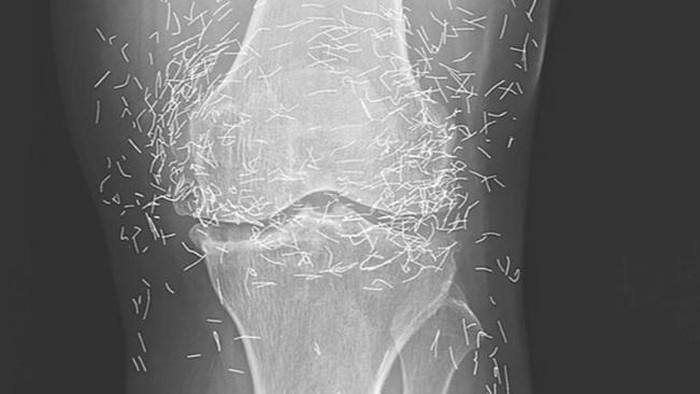

Jakarta - Belum lama ini heboh gambar rontgen penemuan benang 'susuk' emas di dalam tubuh seorang pasien di Korea Selatan. Ternyata, ini bukan kejadian yang pertama.